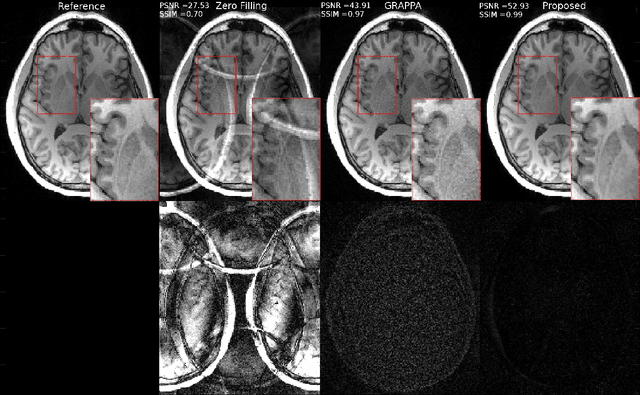

Fast data acquisition in Magnetic Resonance Imaging (MRI) is vastly in demand and scan time directly depends on the number of acquired k-space samples. Conventional MRI reconstruction methods for fast MRI acquisition mostly relied on different regularizers which represent analytical models of sparsity. However, recent data-driven methods based on deep learning has resulted in promising improvements in image reconstruction algorithms. In this paper, we propose a deep plug-and-play prior framework for parallel MRI reconstruction problems which utilize a deep neural network (DNN) as an advanced denoiser within an iterative method. This, in turn, enables rapid acquisition of MR images with improved image quality. The proposed method was compared with the reconstructions using the clinical gold standard GRAPPA method. Our results with undersampled data demonstrate that our method can deliver considerably higher quality images at high acceleration factors in comparison to clinical gold standard method for MRI reconstructions. Our proposed reconstruction enables an increase in acceleration factor, and a reduction in acquisition time while maintaining high image quality.